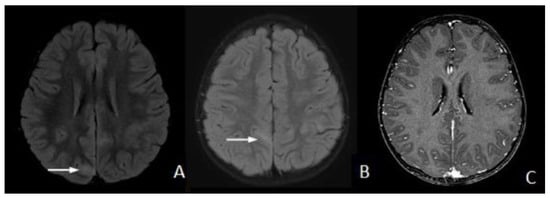

FLAIR Hyperintense Cortical Lesions in a 4-Year-Old Child with Myelin Oligodendrocyte Glycoprotein (MOG)-Associated Encephalitis and Seizures: A Case Report

2. Case Presentation